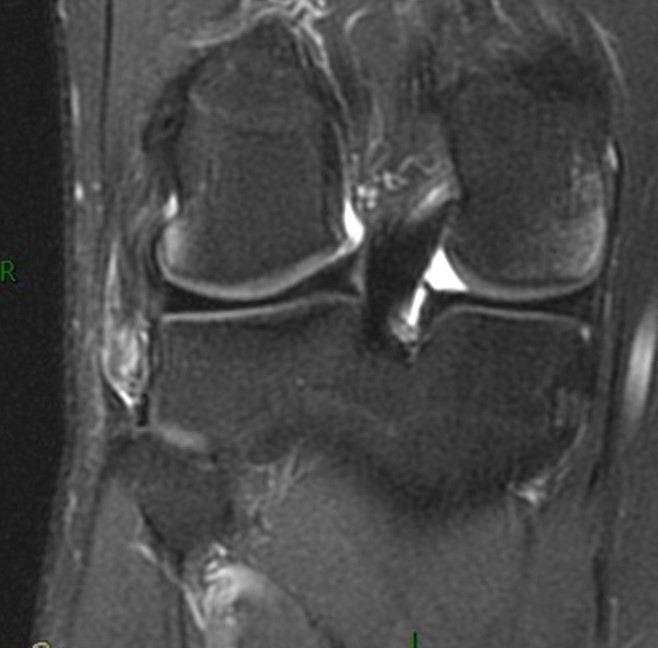

Slide6.JPG